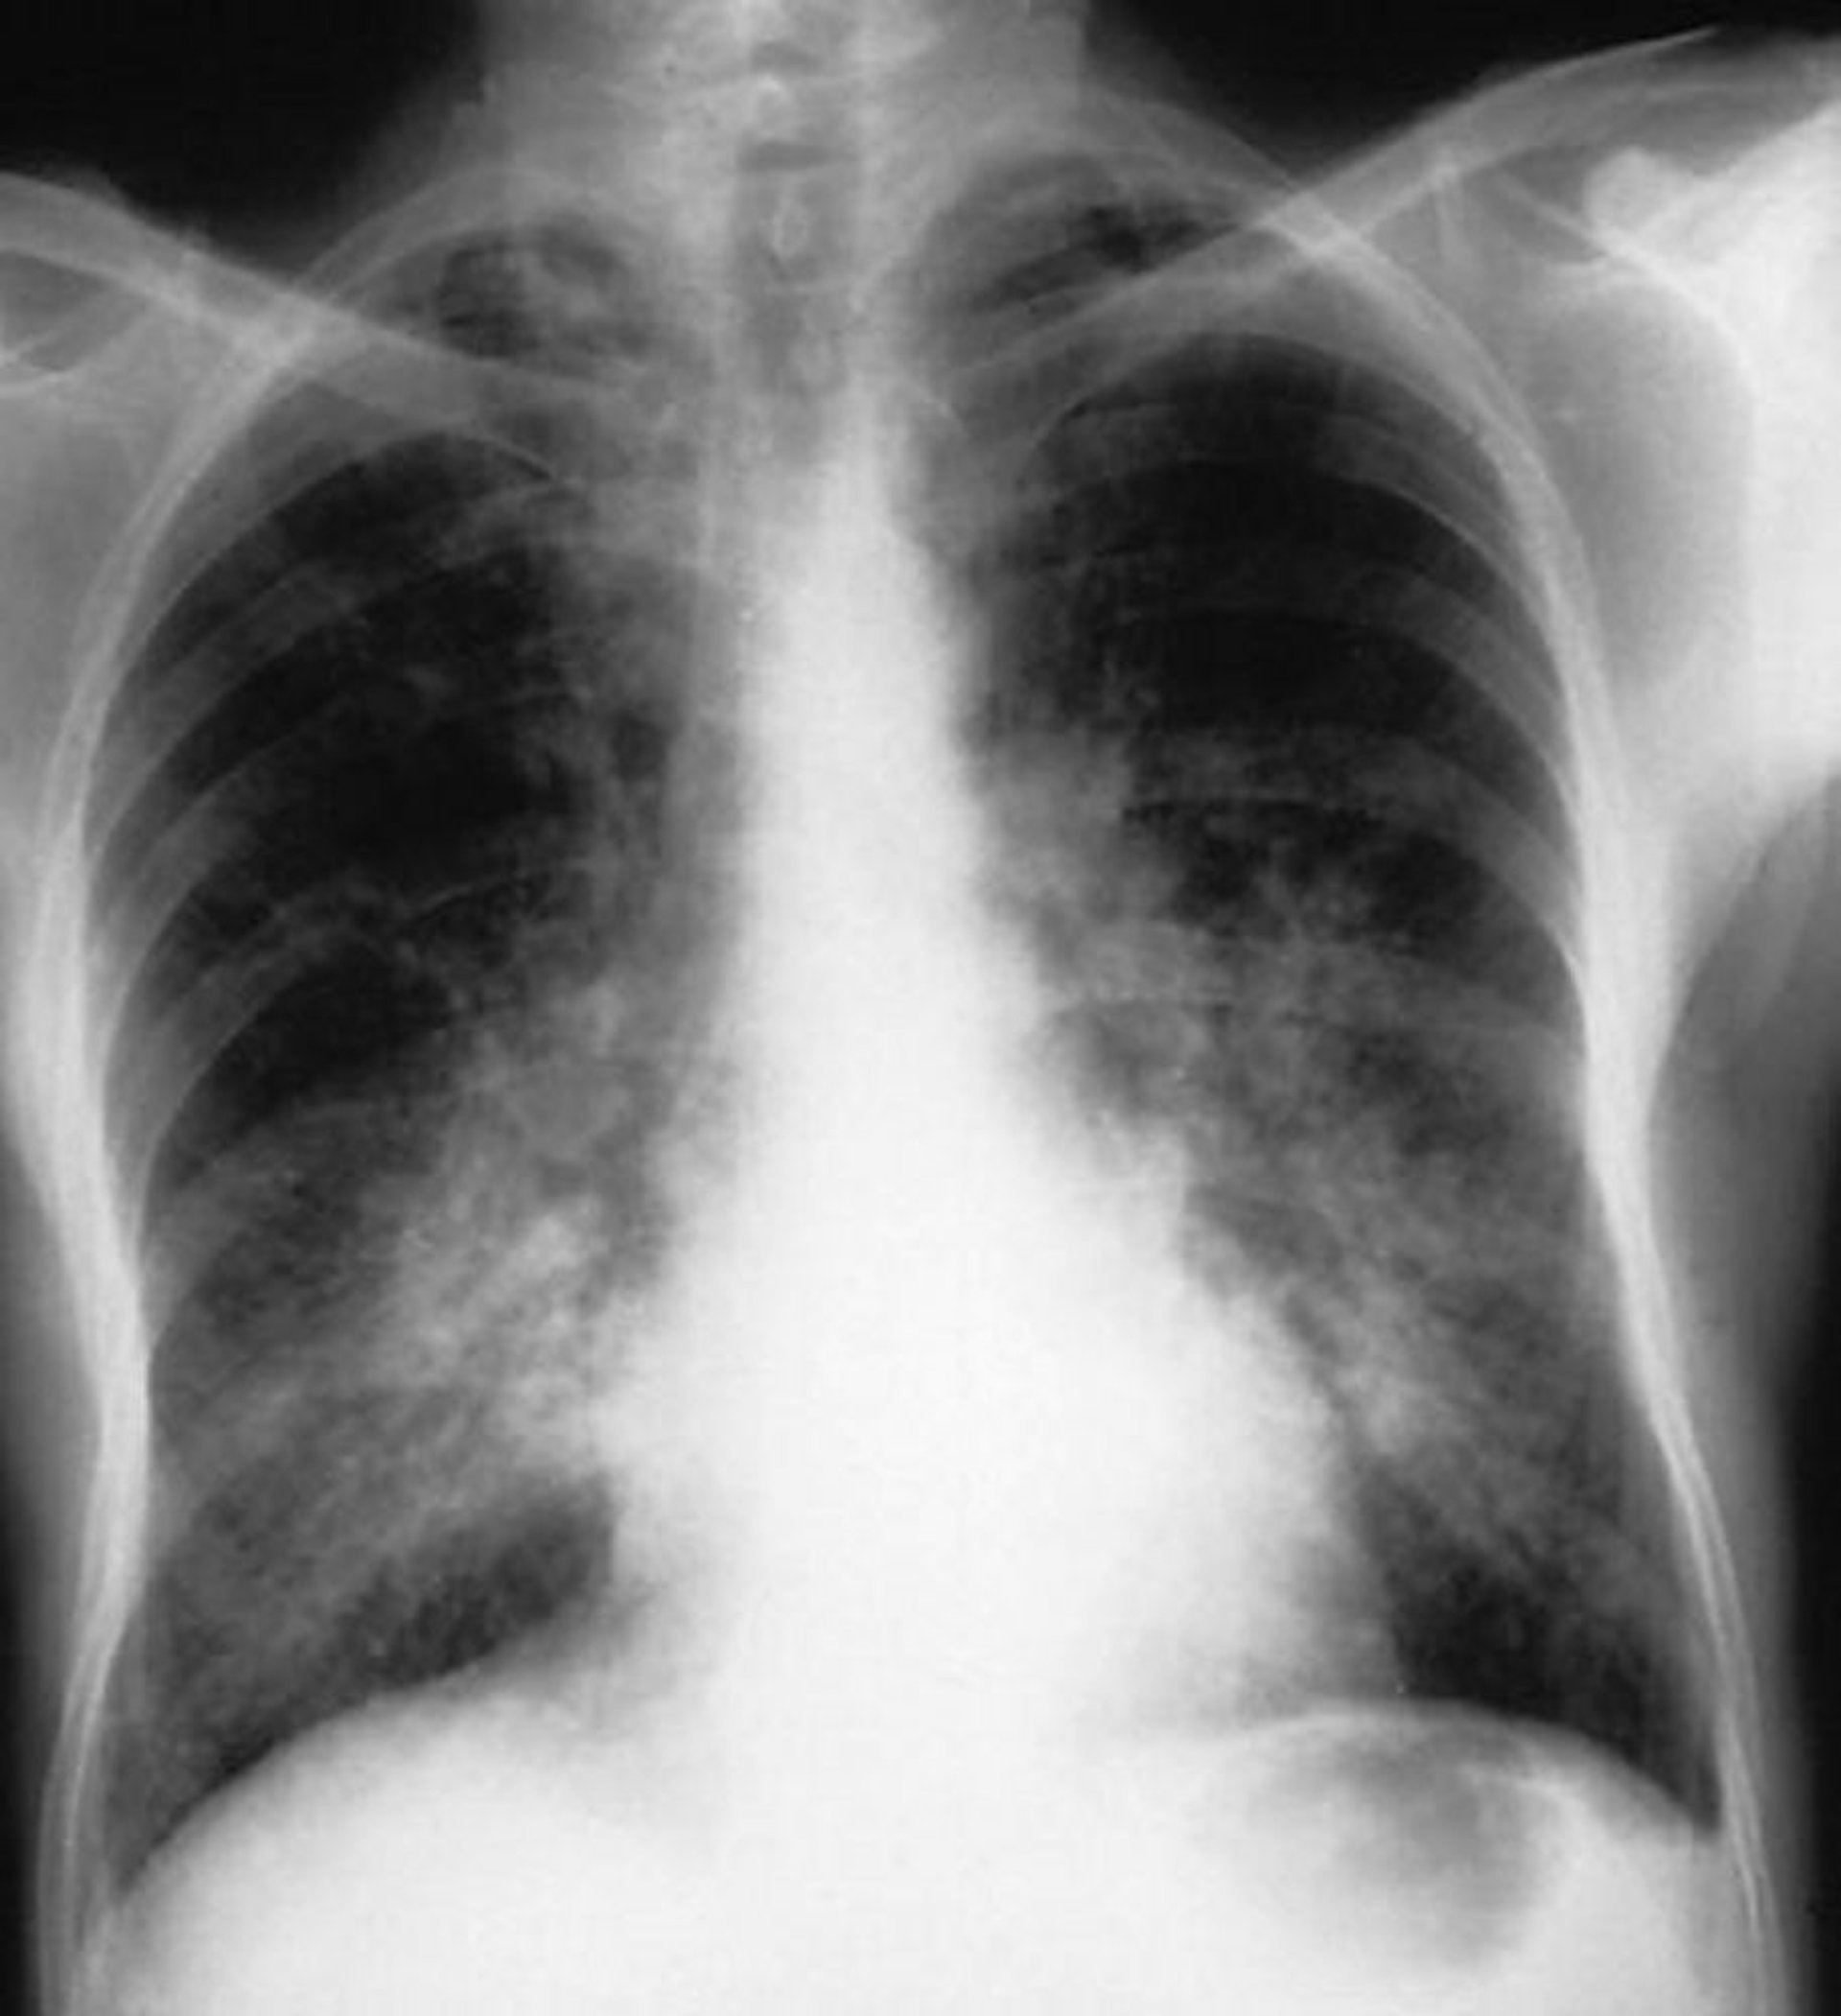

Альвеолярное кровотечение (синдром Гудпасчера)

Двусторонние альвеолярные затемнения у пациента с альвеолярным кровоизлиянием вследствие синдрома Гудпасчера.

By permission of the publisher. From Cohen A, Glassock R. In Atlas of Diseases of the Kidney: Glomerulonephritis and Vasculitis. Edited by R Schrier (series editor), RJ Glassock, and AH Cohen. Philadelphia, Current Medicine, 1999.